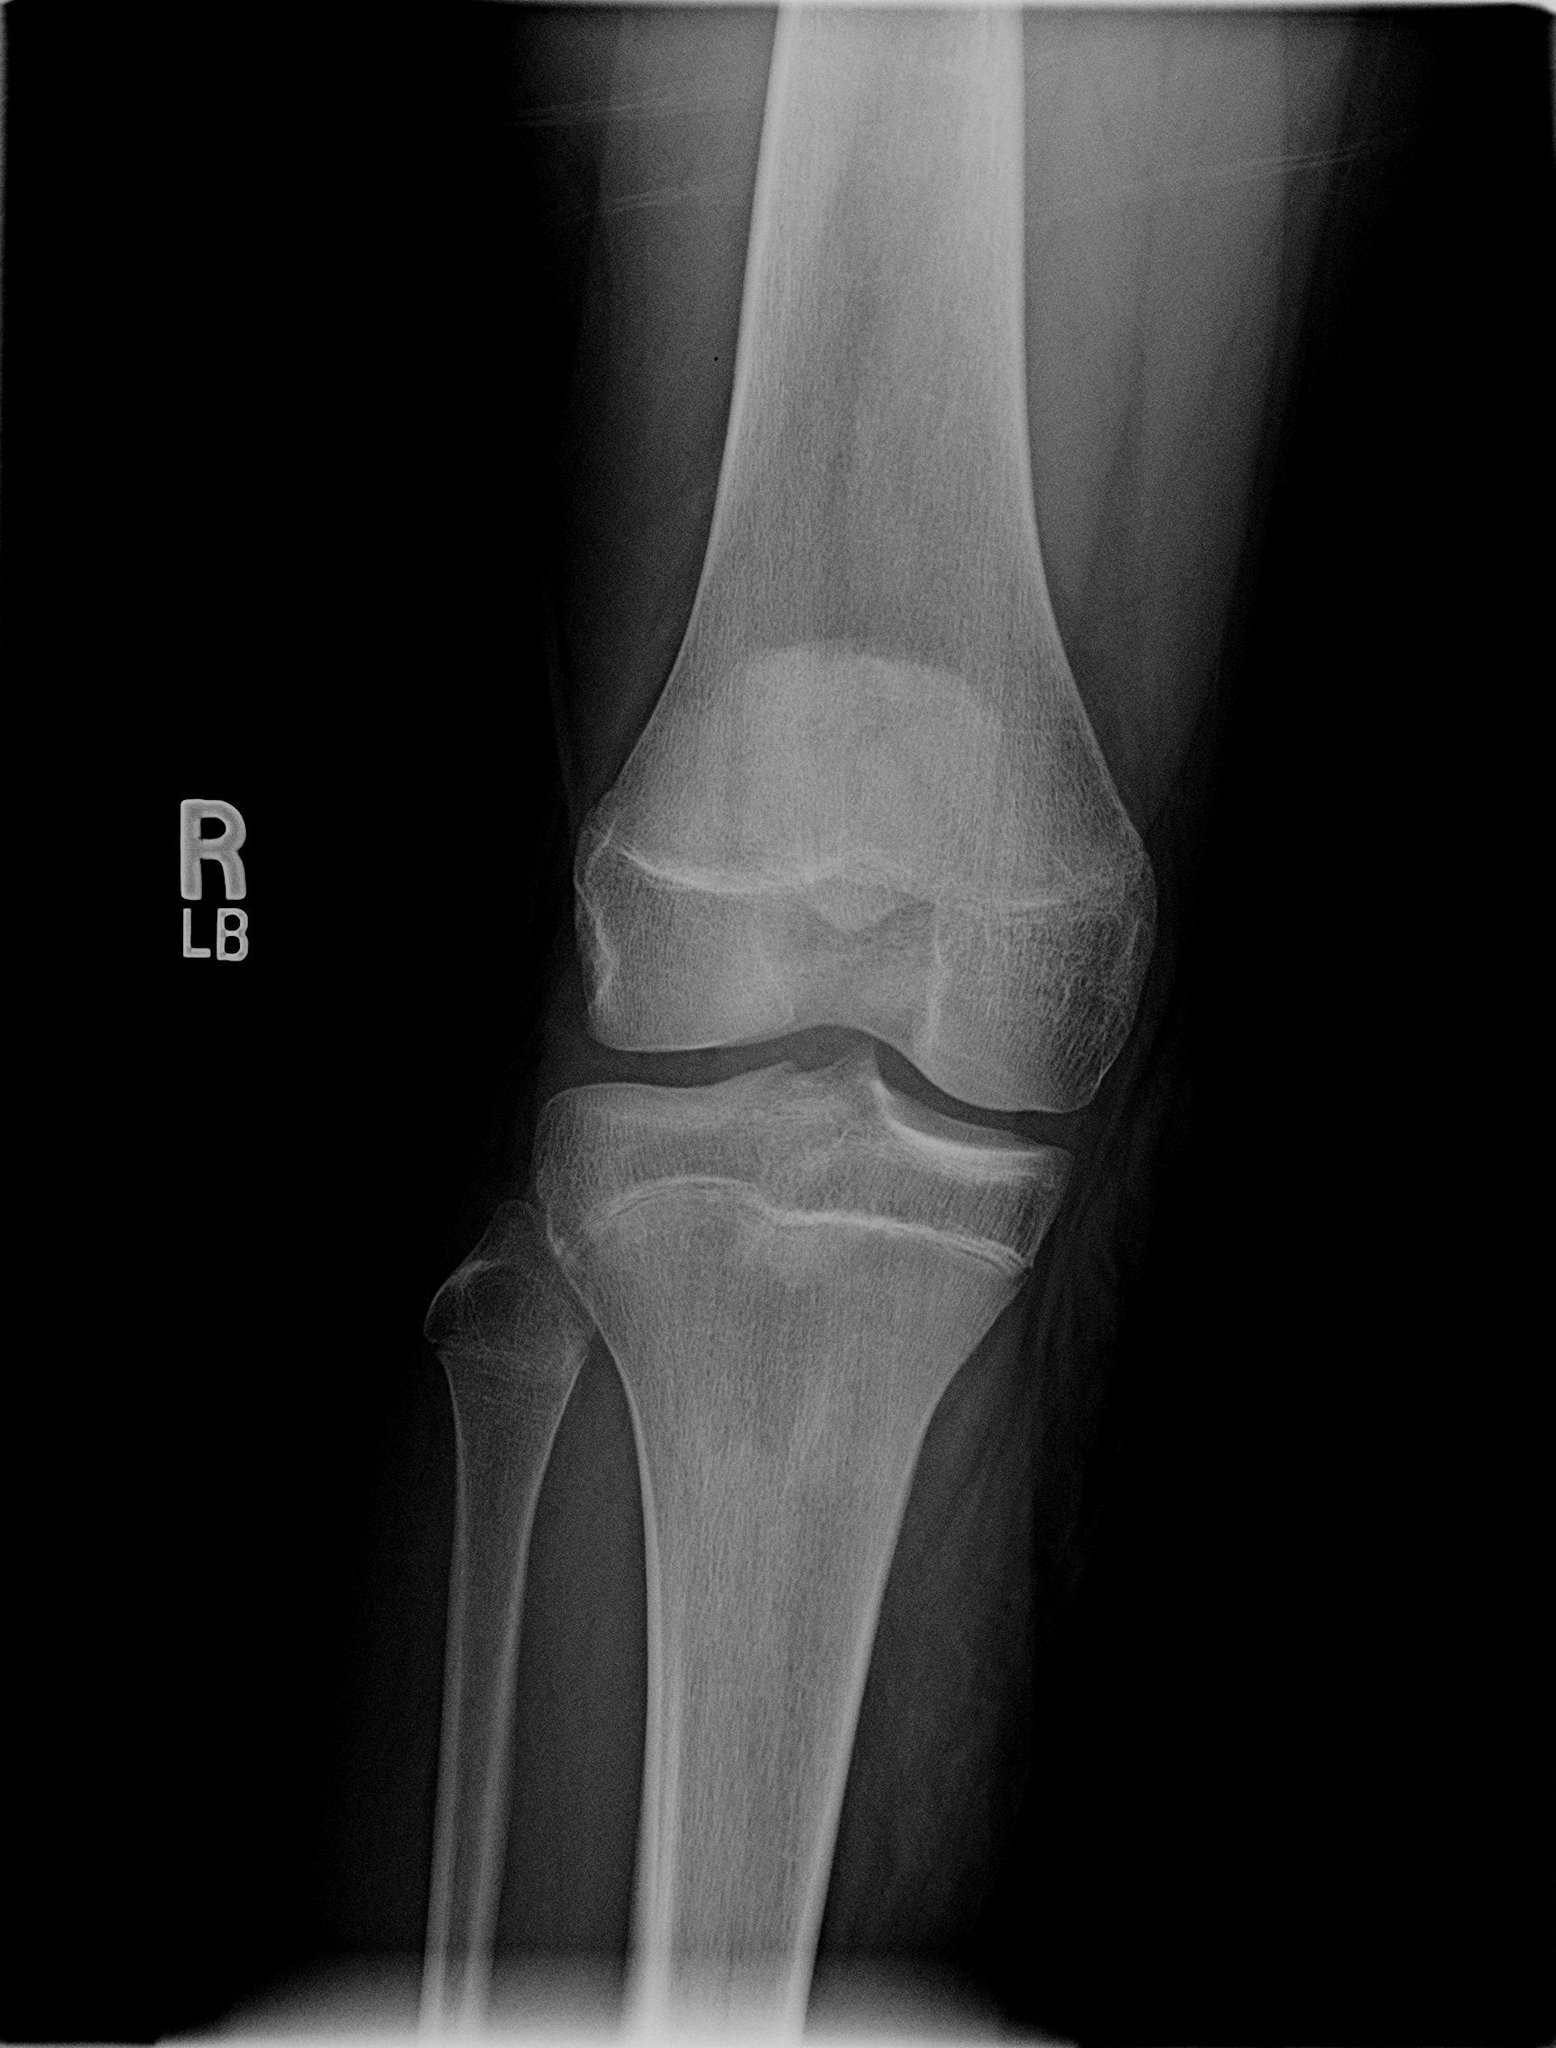

Inner knee pain may be caused by a sprain or tear in the medial collateral ligament or mcl. This is usually caused by an injury where there has been excessive twisting and. The knee plays a very important role in various bodily functions and movements such as walking, running, and jumping. As much as possible, try to avoid things that make it hurt worse, like running, squatting, lunging. However, when anything which interferes with the way the kneecap moves, the force exerted on the kneecap is greatly magnified. Inside knee pain when walking: Are you looking for the best medial knee pain running shoes? Typically, knee pain is accompanied by clicking or crunching sound when one starts running.

Then you must be surely looking for some ways to treat self and get the necessary relief to your knees. The knee is a large and complex joint. It also has other surrounding structures like the tibia and kneecap. The pain may also get exacerbated especially when running downhill. The two most common causes of meniscal tears are due to traumatic injury (often seen in athletes) and degenerative processes (seen in elderly patients who. Are you having knee pain while walking downstairs? Medial knee pain refers to pain existing in the inner knee. It usually starts with lateral knee pain during and after runs, but there are two major types. While some knee pain is instantaneous, medial knee pain usually develops avoid running downhill. Understanding the causes of medial knee pain can help you learn how to prevent it and when it might be time to reach out for medical help. The plica, a redundancy of the joint synovium medially, can the pain is aggravated by activity, particularly running downhill and climbing stairs. Outside knee pain and running. Runners more commonly injure the medial meniscus (inside of the knee) rather than the lateral meniscus (outside of the knee).